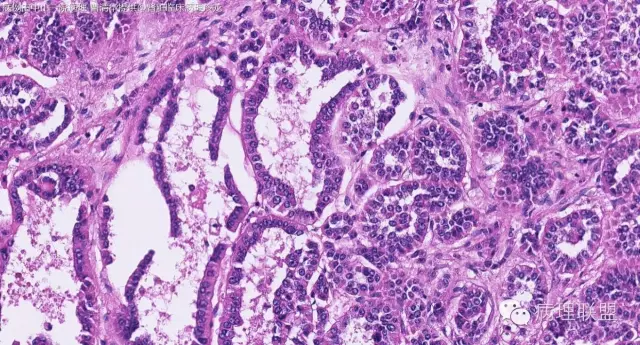

女性,50岁,肾上腺肿物(影像及手术均确认肿物位于肾上腺,界限清楚)。血压升高。(病例由 中山一院病理 曹清华提供,致谢!)

病例讨论

伴假腺样结构的肾上腺皮质腺瘤,合并髓脂肪瘤

从肿瘤的位置及镜下与肾上腺皮质的关系看,应该像是皮质来源肿瘤。假腺样结构的皮质腺瘤没有见过,似乎文献也还没查到。另外inhibina, melanA, syn均阴性(肿瘤旁正常皮质阳)感觉有点迷惑。。。请老师指教,有相关文献么?@武警嘉兴医院 周泉

假腺样是细胞粘附性差了导致。往往可以伴随黏液成分,组化上这几个抗体应该至少会有灶性阳性。

这个我再仔细看下。但,我们这例腺管结构不像是粘附差所致,是真的腺管;间质目前还没有看到有间质粘液变性区域;inhibina, syn, menlana是真的不阳,灶性都没有...